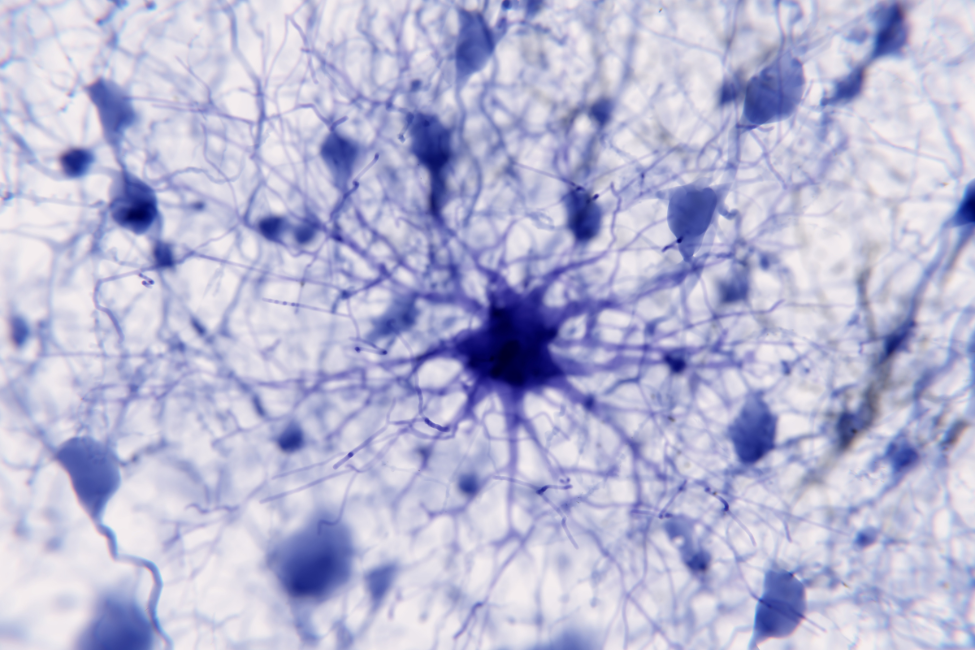

The Role of Microglia in Brain Health

Microglia are essential immune cells in the brain, previously seen as simple supporters of neurons but now understood as specialized resident macrophages of the central nervous system (CNS), actively involved in clearing protein aggregates, maintaining the blood-brain barrier, and regulating neuroinflammation.